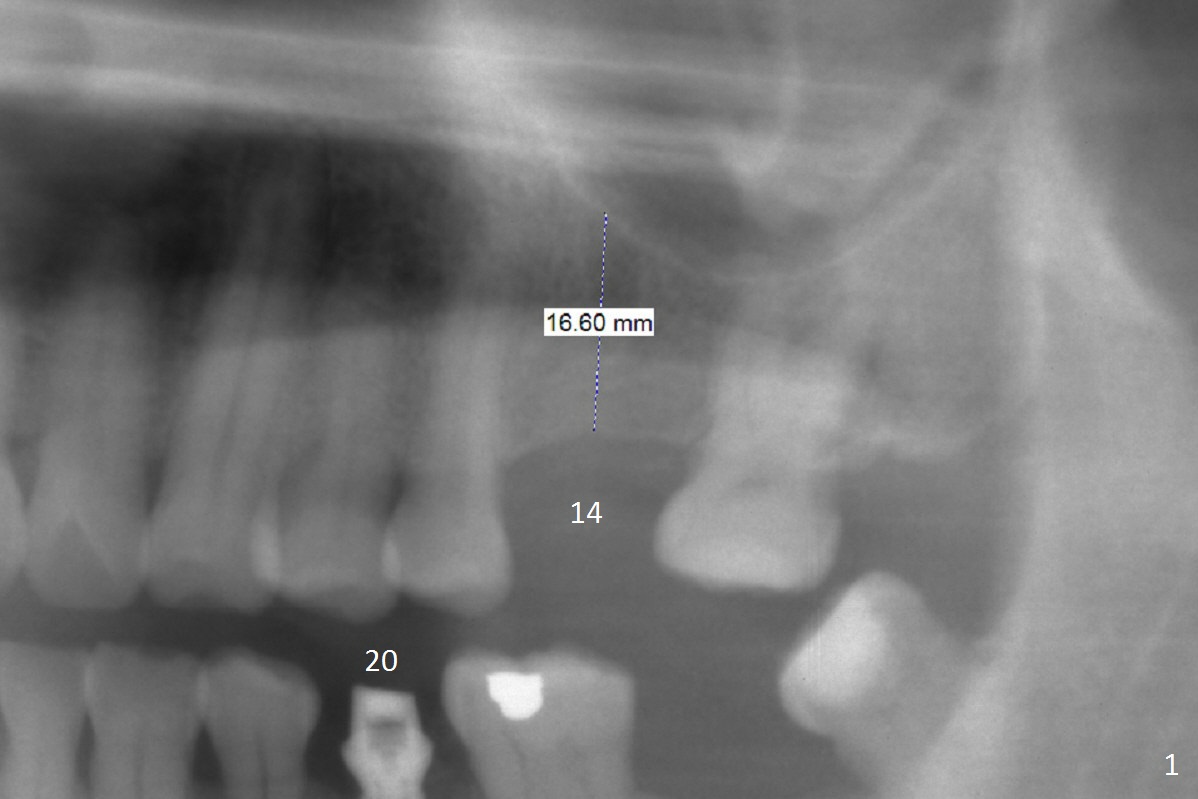

The 54-year-old man will return for #14 implant placement 1 month post the one at #20 (Fig.1). If the bone is wide or moderate, use 1.6 mm drill with possible drill extension to penetrate the mucosa and start osteotomy at the depth of 18 mm, followed by DIO bone expanders. The bone density of this patient is expected to be high. What extra kit should be prepared?

The tip of the initial osteotomy should be mesial to compensate for distal tendency when the osteotomy increases at the sloped sinus floor.